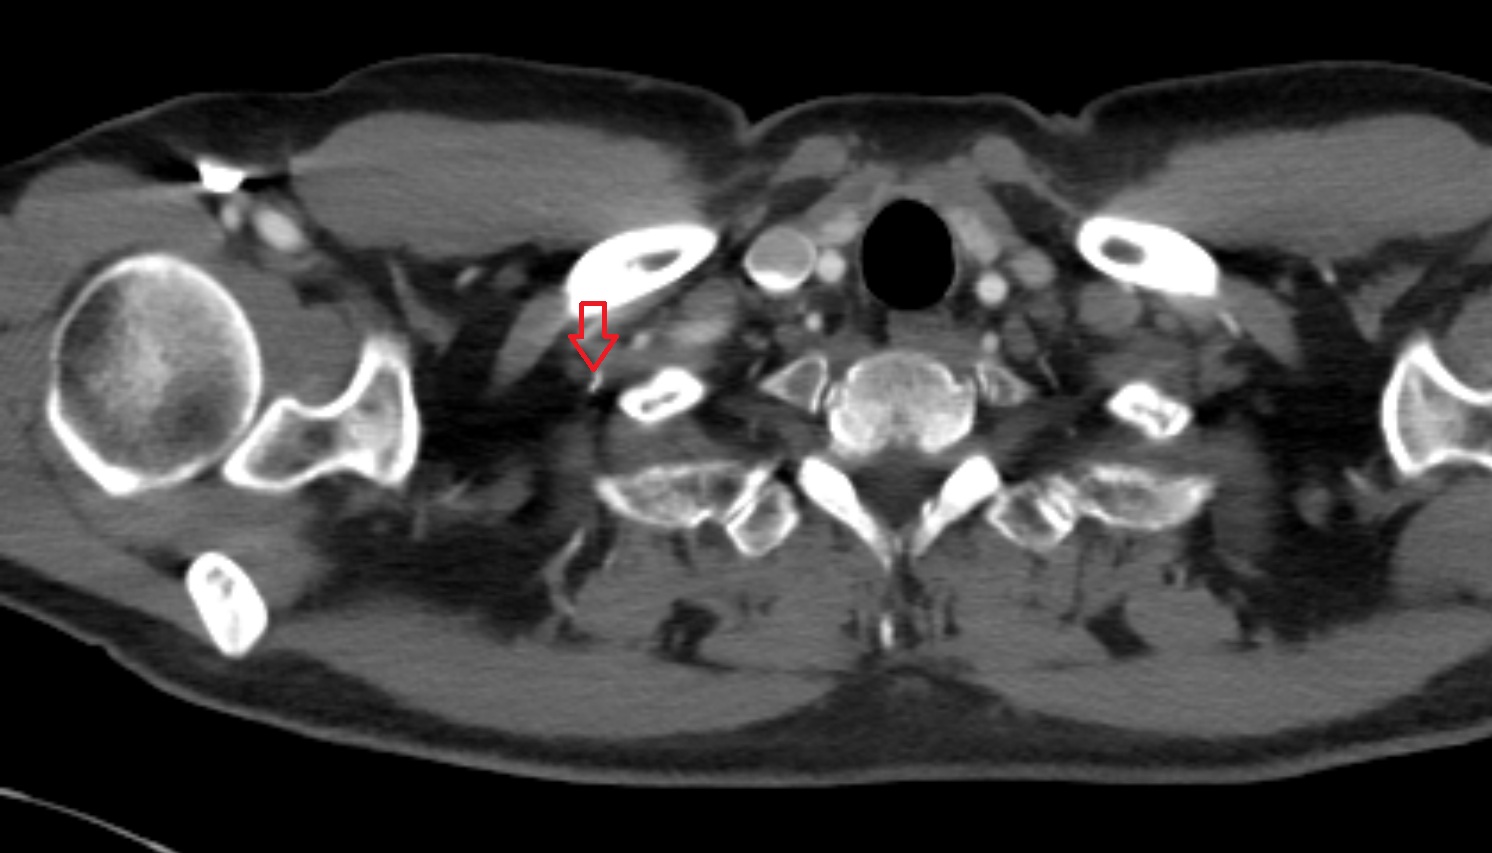

- Internal carotid artery (cervical part)

- Carotid bifurcation

- Common carotid artery

- External carotid artery

- Subclavian artery